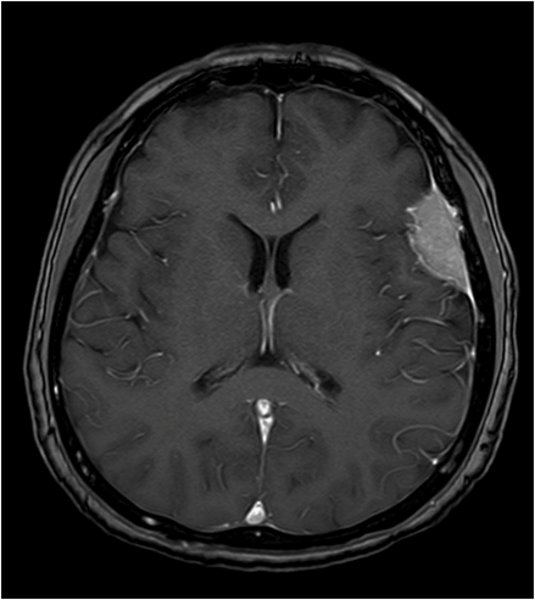

Konvexitätsmeningeom - T1 mit KM